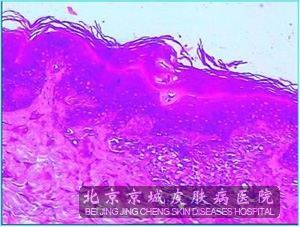

原发性淀粉样变常见表现原发性淀粉样变常见表现有哪些呢?原发性淀粉样变患者一般会伴有明显的皮肤损害,而且本病的淀粉样蛋白的化学起源是表皮中的角蛋白,由变性的表皮*逸入 中并转化成淀粉样蛋白沉积在 乳头内致病的。那么原发性淀粉样变常见表现有哪些呢?

原发性淀粉样变常见表现一般比较好,但是表现为好发于中年女性,常发生于上背,颈,胫前,乳房,大腿很臀部等处的斑状淀粉样变,皮疹为灰色,蓝色或褐色的色素沉着斑呈网状或波纹状,可无自觉症状或仅有轻度瘙痒等损害,而苔藓样淀粉样变好发于胫前,臂外侧和背部等部位。